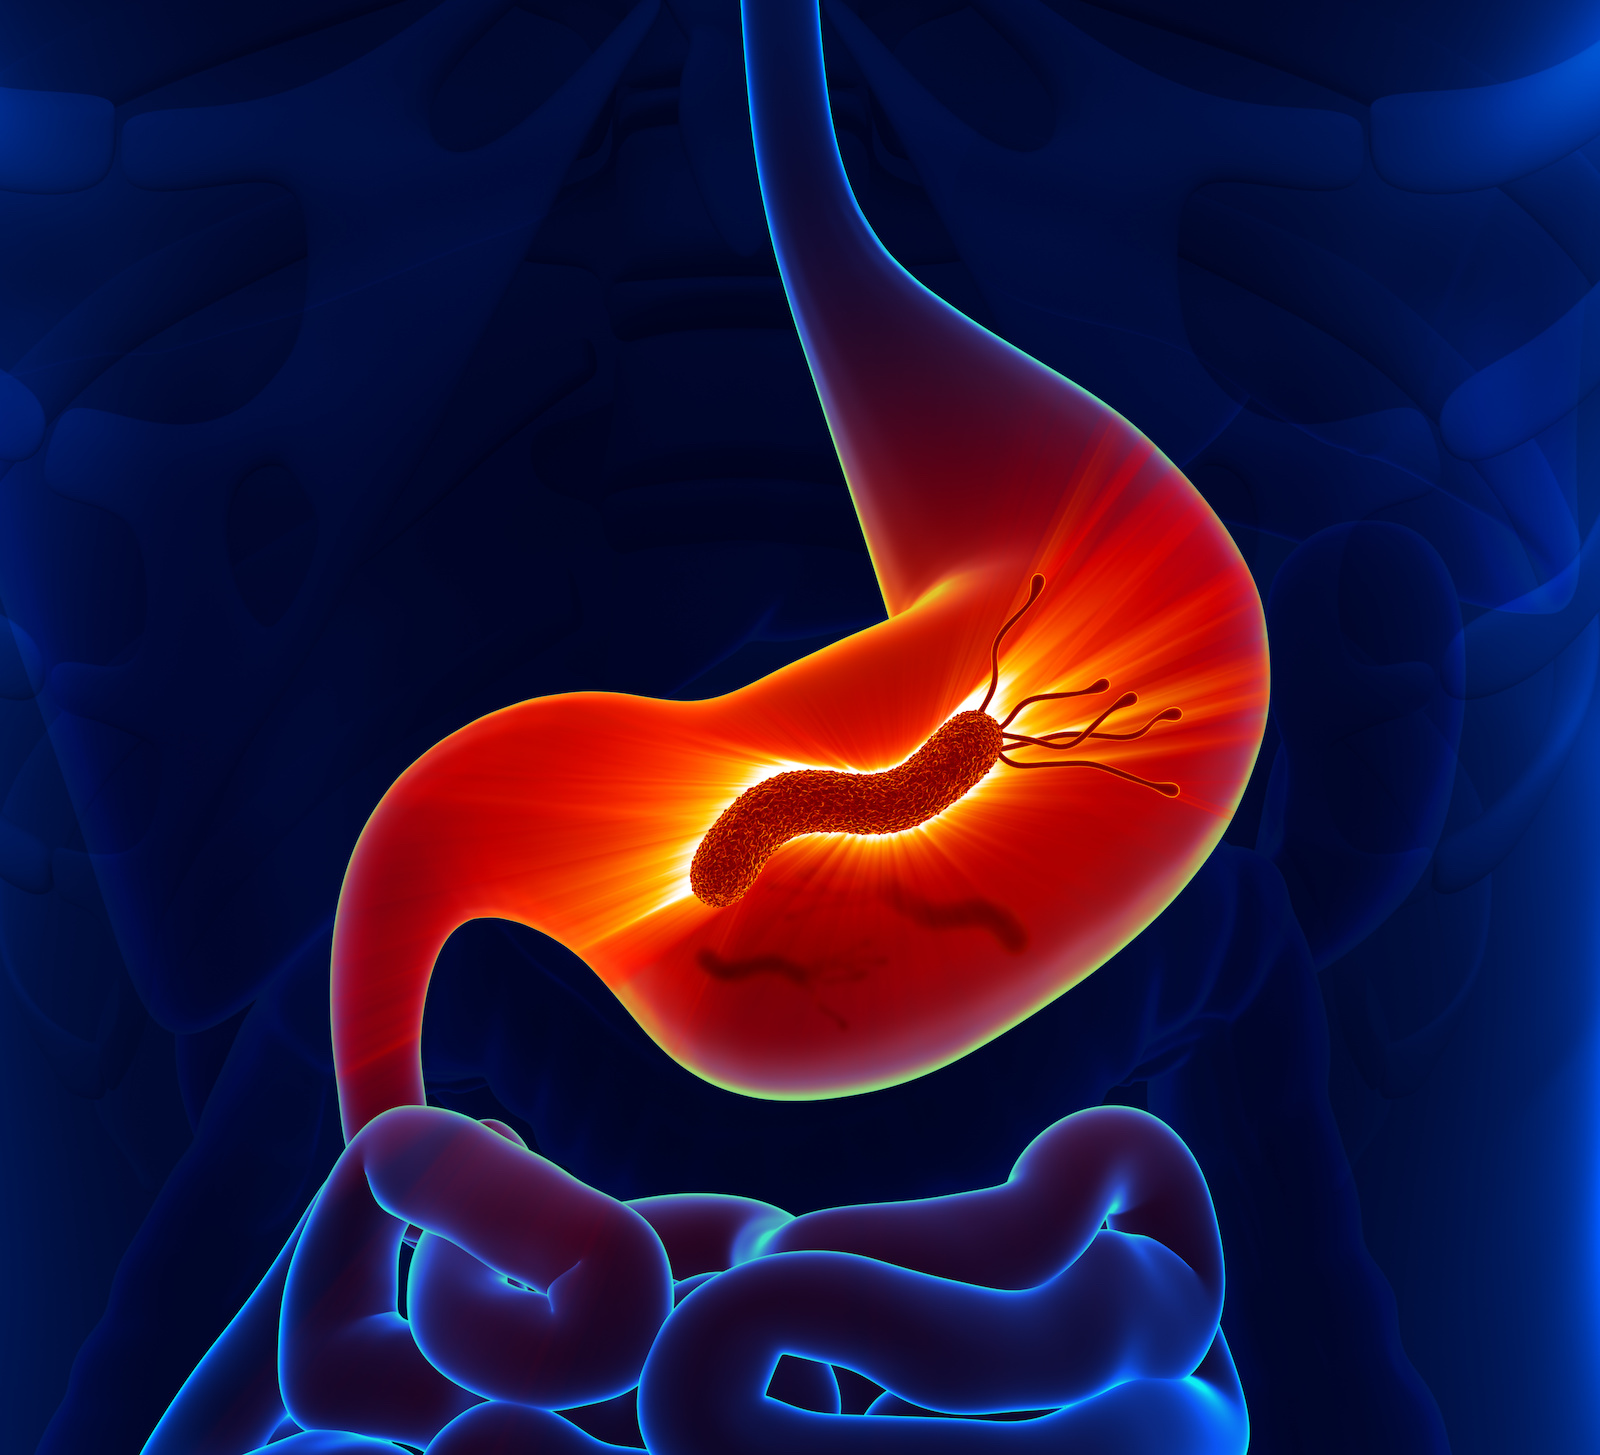

Gastric Cancer Foundation How inflammation causes gastric cancer …

Gastric Cancer, Acid Reflux, Helicobacter Infection | HK Surgeon